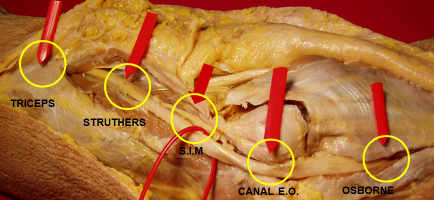

El nervio cubital a lo largo de su recorrido desde el tercio medio del brazo hasta su entrada en el tercio proximal del antebrazo puede estar comprimido en 5 zonas:

1. Arcada de Struthers,

2. Septo intermuscular medial,

3. Canal epitrocleo-olecraniano,

4. Ligamento arcuato y en

5. La arcada de Osborne (figura 1)

Figura 2: posibles zonas de compresión del nervio cubital en codo